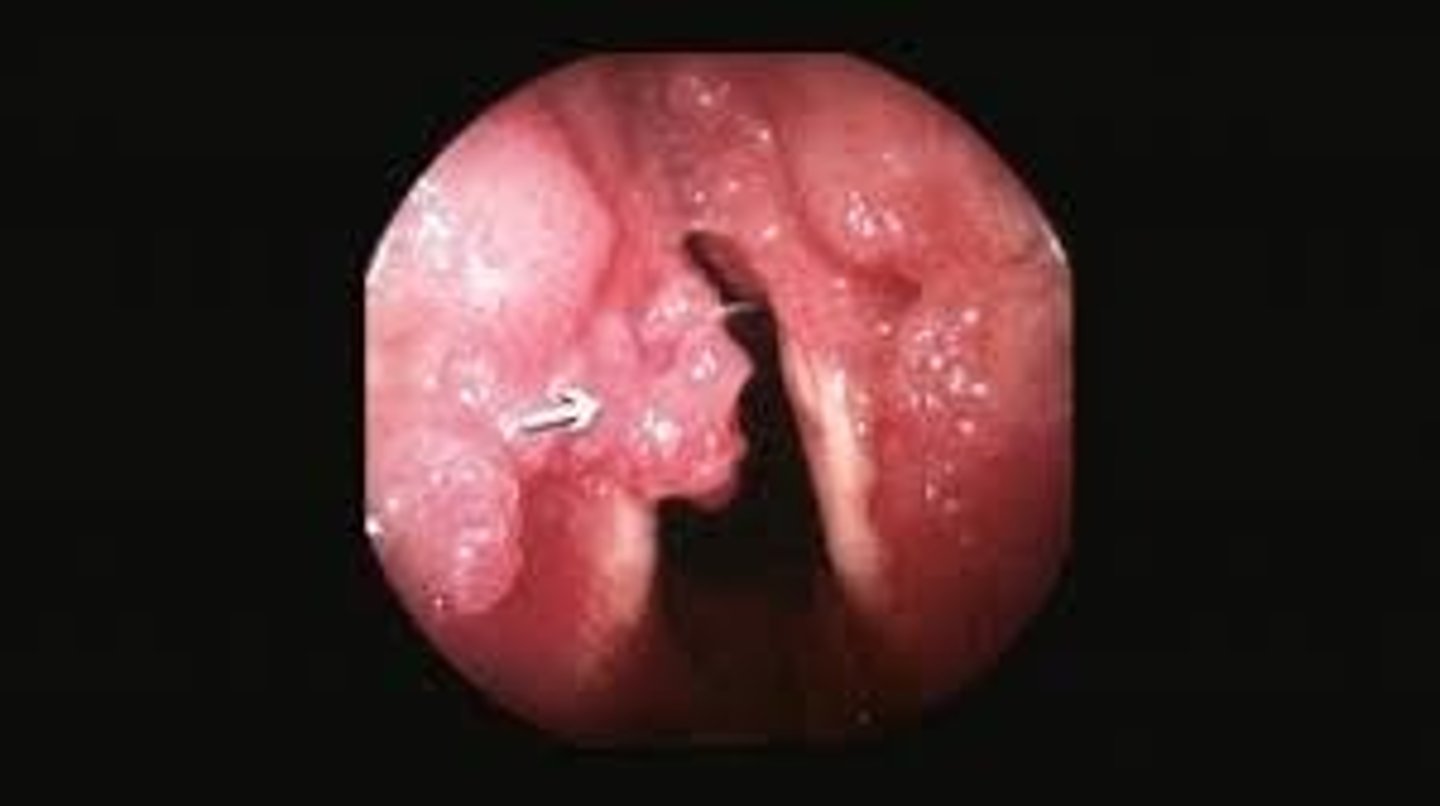

What causes papilloma on the vocal folds?

Human papillomavirus (HPV).